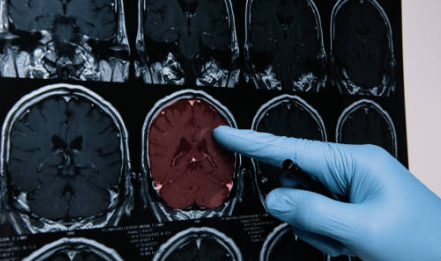

모야모야병 썸네일 모야모야병(Moyamoya Disease)은 뇌혈관이 점점 좁아지면서 혈류가 줄어들어, 뇌에 충분한 혈액 공급이 어려워지는 희귀 질환입니다. 이로 인해 뇌혈류가 부족해져 뇌졸중, 일과성 허혈 발작(TIA), 뇌출혈 등의 증상을 일으킬 수 있습니다.

모야모야병 환자에게는 혈관이 비정상적으로 얇아지거나, 기존의 큰 혈관이 좁아지면서 뇌에 작은 새로운 혈관들이 생겨나는 현상이 나타납니다. 이러한 혈관들은 정상적인 혈류를 유지하기에 충분하지 않아, 뇌혈류가 감소하고 혈액이 부족해지는 증상을 일으킬 수 있습니다.

특히 내경동맥과 그 주변 부위에 협착이 발생하면서 모야모야병의 대표적인 특징인 "모야모야 혈관"이라는 뿌연 연기 같은 작은 혈관들이 생겨납니다. 이는 정상적으로 형성된 혈관이 아닌 비정상적인 대체 혈관들로, 쉽게 막히거나 출혈을 일으킬 수 있습니다.환경적 요인